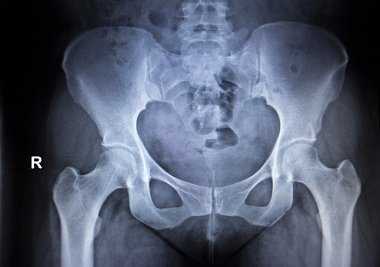

Тазобедренный сустав является самым крупным суставом человеческого тела. Он играет основную роль в поддержании осанки, веса тела, передвижении. Поражение этого сустава приводит к быстрой инвалидизации не только пожилых пациентов, но и лиц молодого возраста.

Начиная обследование, клиницист должен учитывать существование биомеханической взаимосвязи между пояснично-крестцовым отделом позвоночника, крестцово-подвздошными суставами, тазобедренным суставом и нижними конечностями. Это делает необходимым тщательное обследование всех отделов тазового пояса, независимо от характера жалоб пациента.

После опроса врач начинает осмотр. Следует помнить, что при клиническом обследовании пациента с поражением опорно-двигательного аппарата обязательными являются осмотр и сравнение симметричных участков тела. Осмотр проводят в вертикальном и горизонтальном положениях пациента, а также во время ходьбы. Довольно часто пациенты с поражением тазобедренного сустава принимают вынужденное положение – умеренное сгибание, отведение и наружная ротация конечности. При вертикальном положении пациента осмотр проводят спереди, сбоку, сзади. Уже во время осмотра врач может выявить признаки поражения тазобедренного сустава, о чем свидетельствуют разный уровень расположения передних верхних остей и гребней подвздошных костей, ассиметрия ягодичных складок, наличие чрезмерного поясничного лордоза. В горизонтальном положении пациента можно определить наличие сгибательной контрактуры, наружной ротации или приводящей контрактуры тазобедренного сустава. При выраженной сгибательной контрактуре пациент не может полностью выпрямить ногу. При фиксированной приводящей контрактуре пораженная конечность может перекрещивать другую. При оценке положения пяток по отношению друг к другу можно выявить укорочение конечности.

После осмотра проводят пальпацию следующих анатомических структур: передней верхней и задней остей подвздошной кости, гребня подвздошной кости, симфиза, задней верхней ости подвздошной кости, бугристости седалищной кости, ягодичных складок, большого вертела бедренной кости [5]. Определение боли при движениях заменяет пальпацию непосредственно в тазобедренных суставах. Пальпация в паховой области позволяет выявить болезненность при наличии энтезопатии приводящих мышц сустава. При положении пациента лежа на боку следует пальпировать область большого вертела большеберцовой кости для выявления болезненности при вертельном бурсите или энтезопатии отводящих мышц тазобедренного сустава.